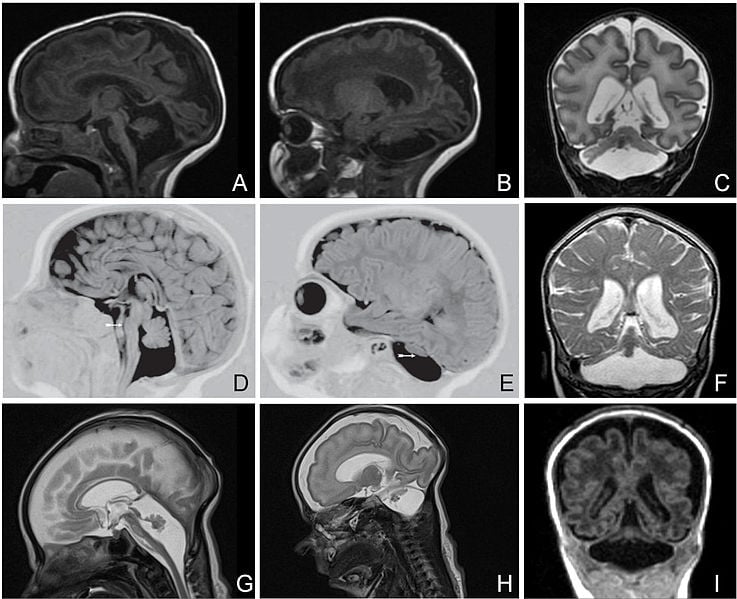

Pontocerebellar hypoplasia is a group of rare, related genetic neurological disorders characterized by abnormal development of the brain, resulting in disabilities in movement and cognitive function. Most patients do not survive to adulthood.

Image Source: The Pontocerebellar hypoplasia MRI image is credited to Yasmin Namavar, Peter G Barth, Bwee T Poll-The and Frank Baas and is licensed as Creative Commons Attribution 2.0 Generic.